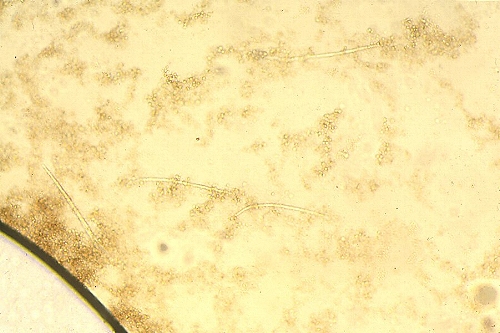

Microfilaire. Examen direct.